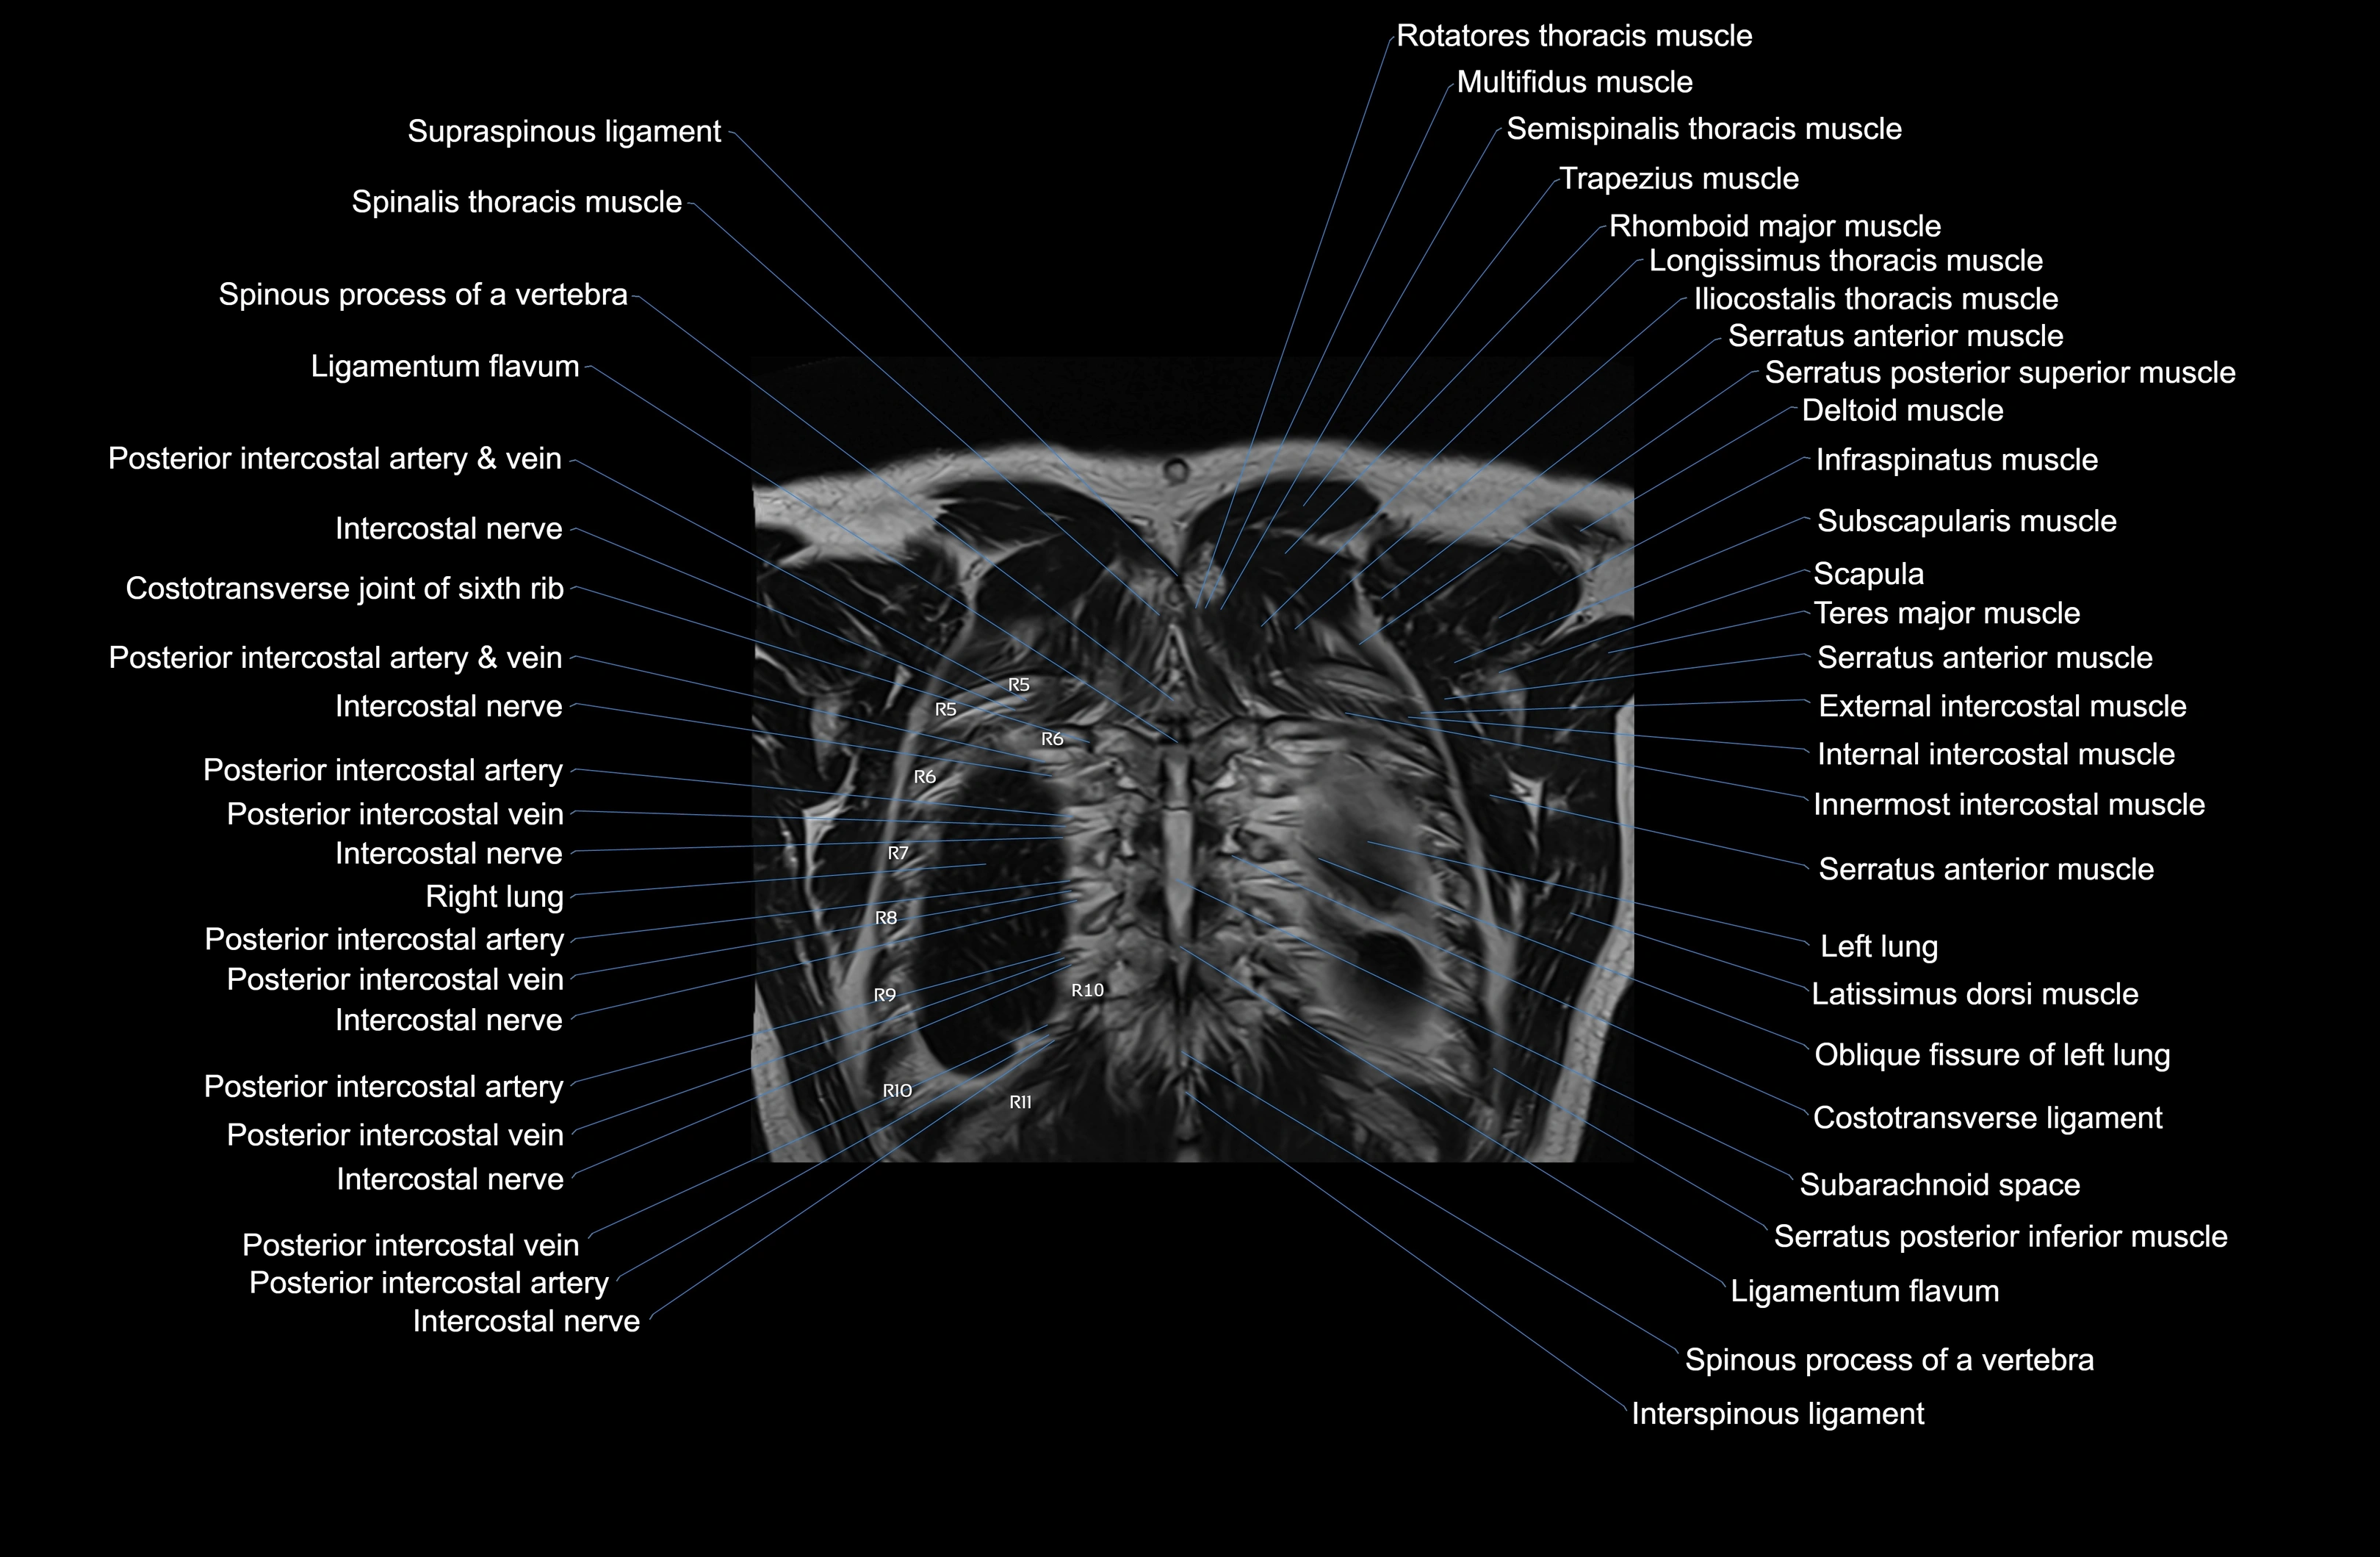

- T (Thoracic spine)